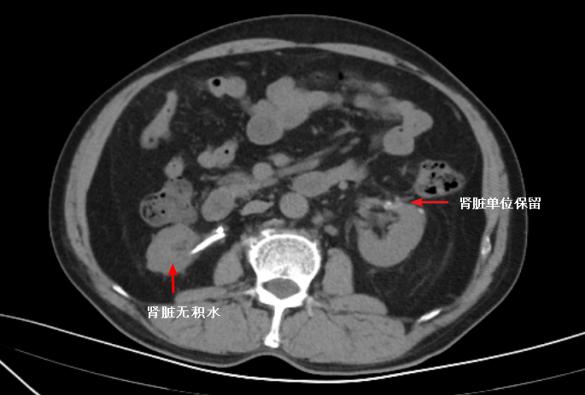

近日,捷克论坛 泌尿四科收治了这样一位年轻的肾癌患者。患者因突发右侧腰痛不适去医院检查,泌尿系CT显示右侧肾脏中度积水,右侧输尿管下段结石,同时发现左侧肾脏外缘直径约4cm占位性病变。医护团队在完善术前准备后,对其进行了右侧输尿管镜钬激光碎石取石术+左侧保留肾单位肾部分切除术手术治疗。术后,患者恢复良好。术后一月复查泌尿系CT,右肾积水完全消失,左侧肾肿瘤完整切除并有效的保留左侧肾脏功能。

泌尿四科近期开展了多例保留肾单位肾部分切除术,术后效果良好。泌尿四科杨科主任医师表示,经过保留肾单位肾部分切除术,不仅能完整切除了肿瘤,同时保护了肾功能。(泌尿四科 谭武宾 毛正)